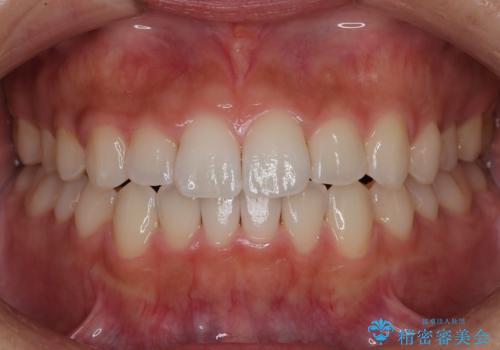

【非抜歯】インビザラインで正しい噛み合わせを

【非抜歯】インビザラインでガタつきと口元を改善!非抜歯でも印象が変わる矯正治療